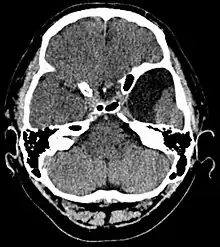

| An MRI of a 25-year-old woman with left frontotemporal arachnoid cyst. | |